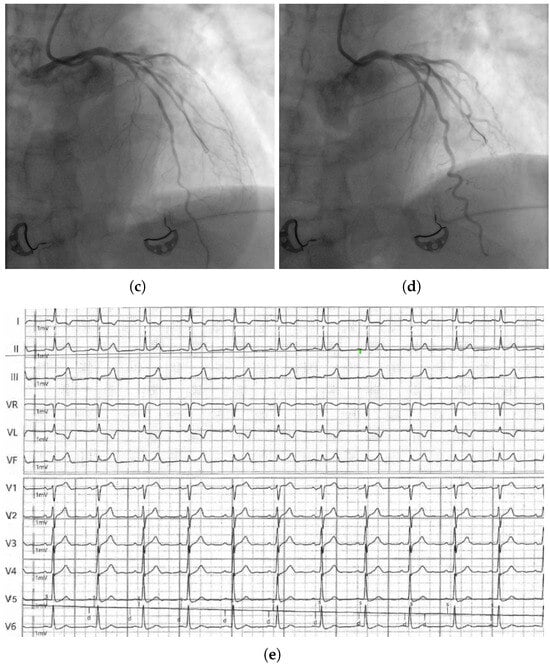

The Great Masquerader: Vasospastic Angina Mimicking Left Main Coronary Artery Disease

A significant proportion of patients undergoing invasive coronary angiography for angina have no obstructive coronary artery disease (CAD). In such patients, coronary microvascular dysfunction (CMD) and vasospastic angina (VSA) represent key pathophysiological mechanisms. We report a case of a 58-year-old male with exertional [...] Read more.

A significant proportion of patients undergoing invasive coronary angiography for angina have no obstructive coronary artery disease (CAD). In such patients, coronary microvascular dysfunction (CMD) and vasospastic angina (VSA) represent key pathophysiological mechanisms. We report a case of a 58-year-old male with exertional chest pain and exercise ECG changes typical of left main or multivessel CAD. Coronary computed tomography angiography (CCTA) showed borderline stenosis of the distal left main coronary artery. Coronary angiography revealed no critical stenosis. A comprehensive functional assessment demonstrated reduced coronary flow reserve (CFR = 2.0) and an elevated index of microcirculatory resistance (IMR = 25), consistent with CMD. An intracoronary acetylcholine provocation test induced severe focal vasospasm of the mid-left anterior descending artery (LAD) with ST-segment elevation and anginal pain, promptly relieved by nitroglycerin, confirming VSA. This case highlights the diagnostic and clinical importance of invasive functional testing in patients with angina and non-obstructive coronary arteries (ANOCA/INOCA). The coexistence of CMD and VSA (two distinct but overlapping pathophysiological endotypes) is increasingly recognized as a marker of adverse prognosis. Functional coronary assessment should be considered in all patients with angina and non-obstructive coronary arteries, as identifying mixed endotypes enables precise, mechanism-guided therapy. Full article